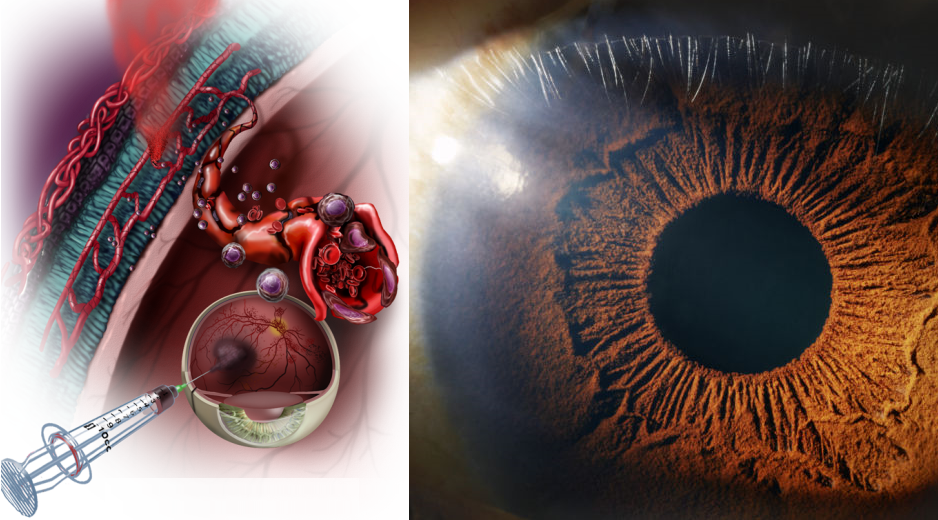

Изображения и анатомия сетчатки глаза